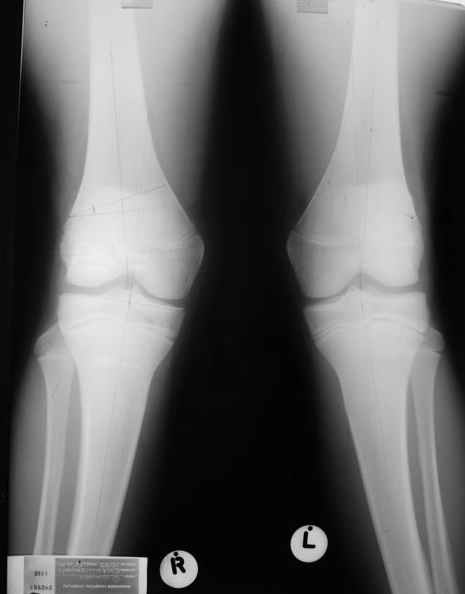

Re: Посстравматическая деформация колена

Как вариант решения прогрессирующей вальгусной деформации коленного сустава я бы предложил косую остеотомию дистального отдела бедра с фиксацией пластиной и компрессирующим винтом.

Не думаю , что артропластика или геми протезирование подходящее решение в этой ситауции.